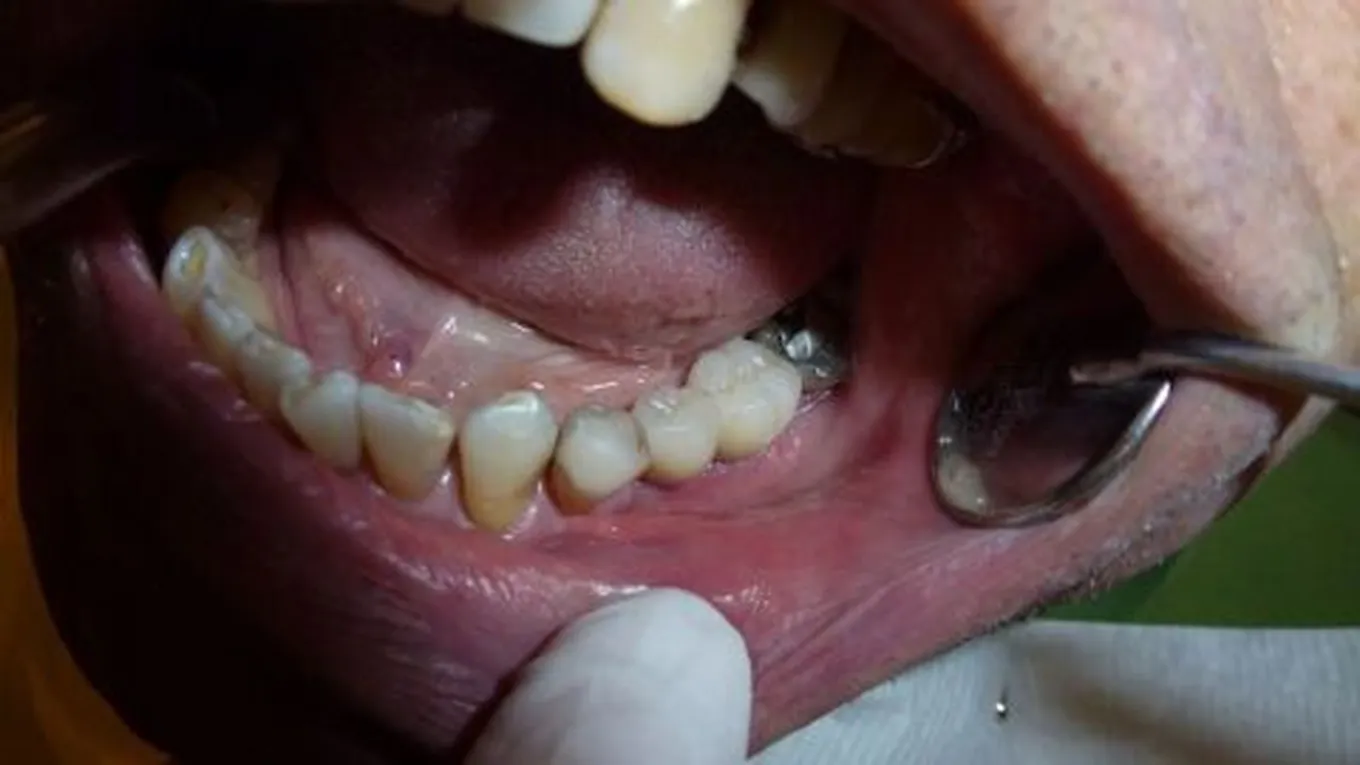

المضاعفات المبكرة لزراعة الأسنان

من الضروري اتباع تعليمات طبيب الأسنان بعد الجراحة لتقليل خطر حدوث مضاعفات، ومن التوجيهات الطبية : الحرص على تناول أغذية طرية غير صلبة، وكذلك تجنب التدخين والمحافظة على نظافة الفم والأسنان، ومن المضاعفات المحتملة بعد زراعة الأسنان نذكر ما يأتي:[2]

- عدوى في موقع الزراعة: يمكن أن تتطور العدوى أثناء وبعد الجراحة، وهناك عوامل تزيد من خطر العدوى مثل: التدخين وعدم الاهتمام بنظافة الفم.

- تحرك الزرعة: يمكن أن تحدث حركات دقيقة للزرعة عندما تفتقر غرسات الأسنان إلى الاستقرار، وعادة يحدث ذلك بعد تركيب السن الصناعي فوراً، ويجدر بالطبيب تركيب السن فوق الزرعة بعد اندماج عظم الفك بشكل صحيح مع الزرعة، لكن في بعض الأحيان يركّب الجراح السن فوراً بعد الزرع، وبهذه الطريقة يتطلب من الشخص عدداً أقل من زيارات الطبيب، لكنها قد تؤدي إلى زيادة الضغط على الزرعة وبالتالي فشل زراعة الأسنان.

- عدم وجود عظم فك كافٍ: يمكن أن تفشل المرحلة المبكرة أيضاً عندما لا يكون هناك عظام كافية لدعم زراعة الأسنان.

- رد فعل تحسسي: يحدث هذا إذا كان المريض يعاني من حساسية تجاه التيتانيوم (بالإنجليزية: Titanium)، وهو المعدن المصنوع منه الزرعات، وتشمل أعراض وعلامات الحساسية التورم، وفقدان التذوق، والإحساس بالوخز.

آثار ومضاعفات متأخرة لزراعة الأسنان

تحدث مضاعفات المرحلة المتأخرة نتيجة لأحداث ضارة طرأت أثناء عملية الجراحة والشفاء، وتتعلق بشكل أساسي بالتحام العظم والأنسجة العظمية المحيطة، وقد تكون المضاعفات الموضعية التي تحدث أثناء جراحة الزرعة هي المحددات الرئيسية لنتائج الزراعة ونجاحها، وبالتالي فإنّ الوقاية من المضاعفات من أولويات الجراح، حيث إنّ الفحص السريري والإشعاعي الدقيق لكل حالة، ووضع خطة علاج مناسبة، واستخدام التقنيات الجراحية والأدوات المناسبة تسهم في منع حدوث هذه المضاعفات، نذكر منها ما يأتي:[3]

- ثقب في السمحاق المخاطي.

- التهاب الجيوب الأنفية للفك العلوي.

- كسر الفك السفلي (بالإنجليزية: Mandibular fracture).

- فشل التحام العظم (بالإنجليزية: Osseointegration).

- آفة زرع محيطية.